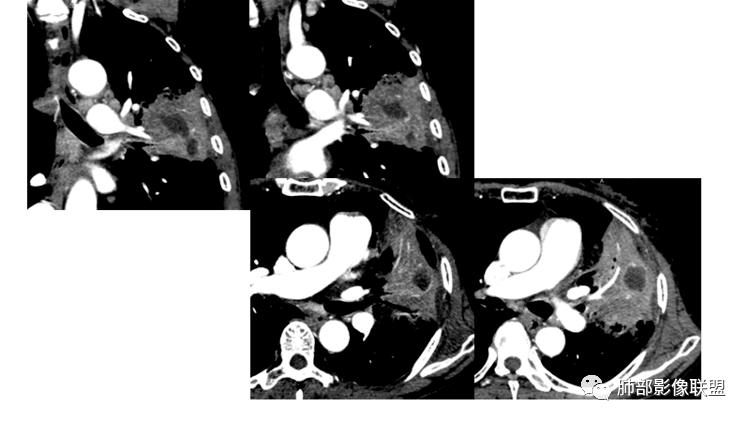

下图:这是中央型肺癌的特点:肺动脉破坏。

腔内肿瘤?肺动脉没有推移,累及多段

形态、边缘、支气管、血管、密度及强化(坏死腔内壁)、淋巴结、与胸膜关系、附近病灶,大概这些分析点

这类病变最好重建出长轴、支气管,这样观察就比较理想

影像上其实也有特点,需要重建观察到支气管情况

下图是炎性的

一般支气管狭窄一些,壁弥漫增厚

今天的病例追到这里断了,腔内病灶有强化就不踏实。

我找几个病例大家看看:

这是炎性特点,壁弥漫增厚,腔内粘液栓

这例也是,只是我调节不理想,壁其实也是弥漫增厚,腔狭窄,腔内粘液栓

这是炎性的,支气管壁弥漫增厚,近端腔狭窄

这是肺癌的

这是腔内肺癌的

南边:

1、局部占位效应,支气管往往增大,而不是支气管狭窄

2、支气管壁破坏、不连续,腔外侵犯

3、占位效应大,局部肺动脉受压外移或侵犯

局部肺动脉没看清楚,支气管壁我没看清楚。占位效应有,这是最不踏实的地方。